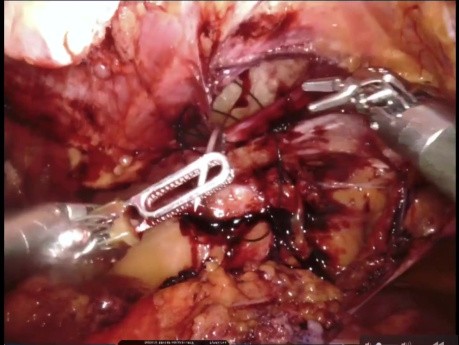

Tratamiento laparoscópico de la hernia inguinal...

¿Quién estaría dispuesto a abordar una hernia inguinal estrangulada por acceso directo después de dos reparaciones abiertas? La mejor opción en estos casos sería la reducción + reparación herniaria...